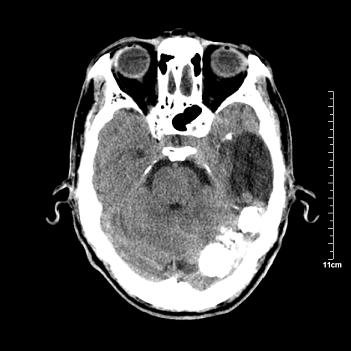

男性患者,72岁,近两天头晕来我院就诊。 因患者血压太高而未做增强,建议病人去市医院做mri检查。等得到mri随访结果再公布给大家。 测及左颞顶枕叶病灶ct值分别为5hu 30hu 729hu。

考虑左侧颞顶枕叶少突胶质细胞瘤。 今天随访患者手术病理结果 病理回报为胶质瘤2级 钙化

左侧颞顶枕叶巨大囊性病灶,灶内见小片实性区且灶内及灶周围大量团块状钙化影,灶周水肿少.左侧室枕角内见环形钙化,可见较清晰前壁,钙化与室壁似有间隙.

考虑1寄生虫病2表皮样囊肿钙化3血管畸形,其他不排

今天追踪患者家属手术病理结果 病理回报为胶质瘤2级并钙化

病理回报为胶质瘤2级并钙化